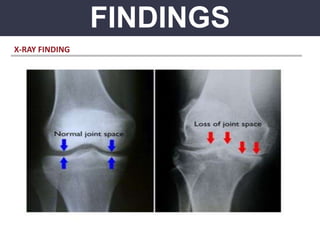

2. IMAGING

 X-ray

Early stage: May look normal except widening of joint space, ultrasound helpful

Late stage: Narrowing and irregularity of joint space; may have OM changes of

adjacent bones

X-RAY FINDING

X-RAY FINDING – WIDENED JOINT SPACE